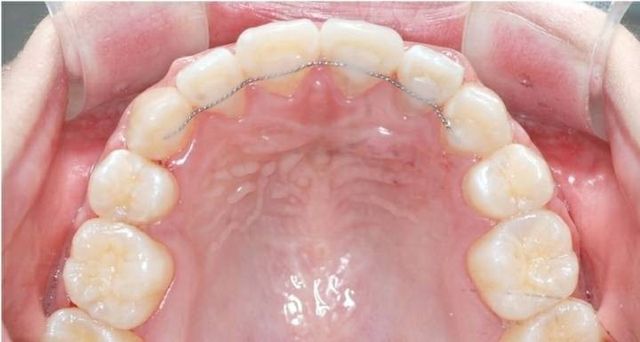

특히 교정 후 유지장치 낀사람은

아랫니 뒤가 진짜 치석과의 전쟁임.